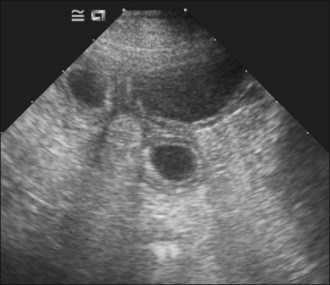

Survey abdominal radiographic findings may be suspicious for intussusception and positive contrast studies are often diagnostic. However, in experienced hands abdominal ultrasonography is the preferred method of diagnosis. A target-like mass consisting of multiple hyperechoic and hypoechoic concentric rings in transverse section (Figure 29.8), or the appearance of multiple hyperechoic and hypoechoic parallel lines in longitudinal section, is considered virtually diagnostic of an intussusception.

Figure 29.8 Target-like ultrasonographic appearance of intussusception in transverse section.

(Photograph courtesy of Andrew Parry)

Case management

An intravenous catheter was placed into a cephalic vein and blood collected for an emergency database that was unremarkable except for mild hypokalaemia. Abdominal ultrasonography revealed a small intestinal intussusception (see Figure 29.8) and exploratory laparotomy was performed.